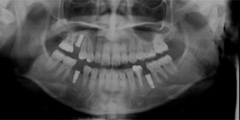

口内写真とパノラマレントゲンを撮影し、まずは顎の骨の状態まで詳しく確認しました。

院長の吉本の診断は以下でした

・歯がない期間が長く続いたため隣の歯が横に倒れてしまい、歯と歯との間に隙間が2ケ所できてしまっていた。

歯がない期間が長く続いたため隣の歯が横に倒れてしまい、歯と歯との間に隙間が2ケ所できてしまっていたため、インプラントの前に矯正治療で隙間をなくす治療を行う